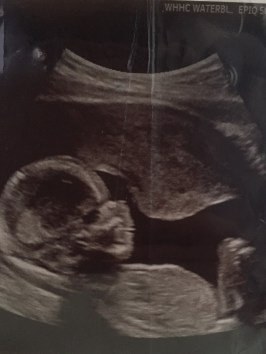

to conceive, to carry, is beyond the diagrams

of human understanding

i think about the journey she made,

to come so far, for so little.